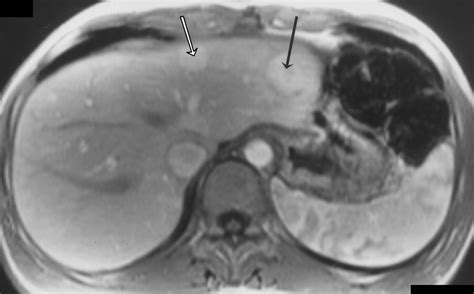

• Magnetic Resonance Imaging (MRI): MRI uses magnetic fields and radio waves to produce detailed images of the liver. It is often the preferred method for diagnosing FNH due to its high sensitivity and specificity.

• focal nodular hyperplasia liver radiology